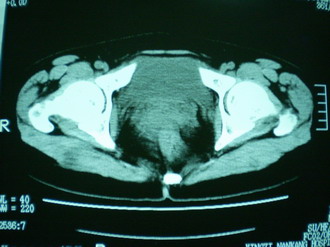

子宫明显前倾,增大,宫颈增大呈分叶状。子宫直肠窝见不规则形水样低密度。(膀胱胀尿不理想)

考虑:1、宫颈部占位;

2、子宫直肠窝少量积液(盆腔炎所致)。

宫颈部肌瘤宫腔内积血,

考虑肌瘤堵塞子宫颈管导致宫腔积液。

考虑:1、宫颈部占位(宫颈癌?);

2、子宫直肠窝少量积液。

1、前曲子宫,2、宫颈部占位?3、盆腔及右输卵管积液?宫内积血?4、左侧卵巢囊肿。